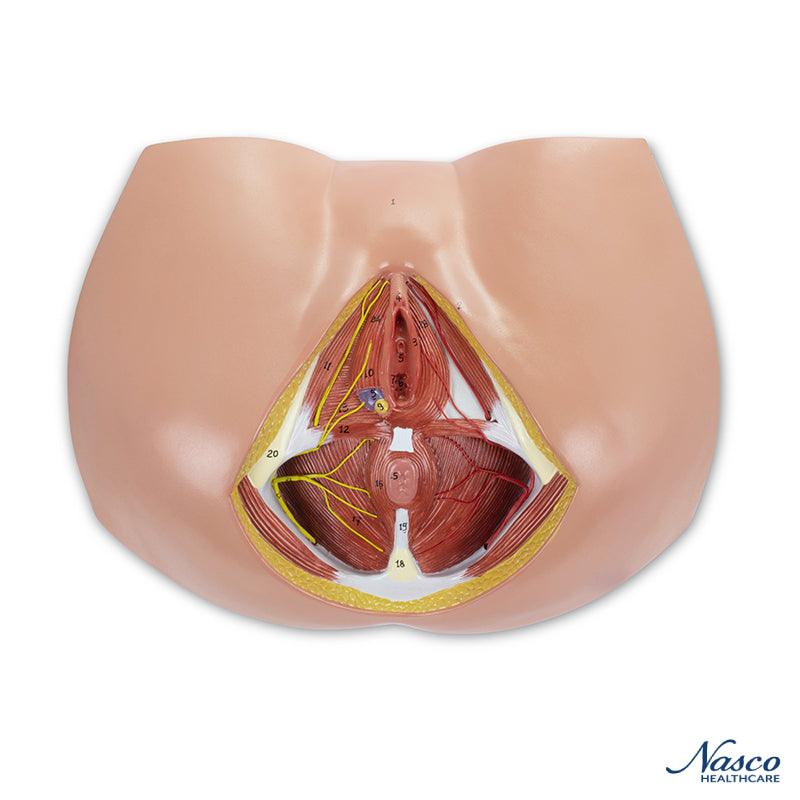

Female Perineum Model

A life-size model showing the female perineum area, including the anus and external genitals. The pelvic diaphragm, urogenital perineum with the opening of the vagina, and anal perineum are well represented. Distribution of blood vessels and nerve endings are included. Accompanying an interactive 3D anatomical model with augmented reality is a great tool to encourage learning and support. This platform allows students to engage in comparative analysis of anatomical models as they compare and contrast the structure of individual organs. This initiative also provides a platform for continuing education, providing opportunities for all students to increase their knowledge of anatomy, physiology and pathophysiology.

One-Year Warranty

Ship Weight (LBs): 3.7 lbs.

Dimensions. (Inches): 16.14 x 10.63 x 8.66